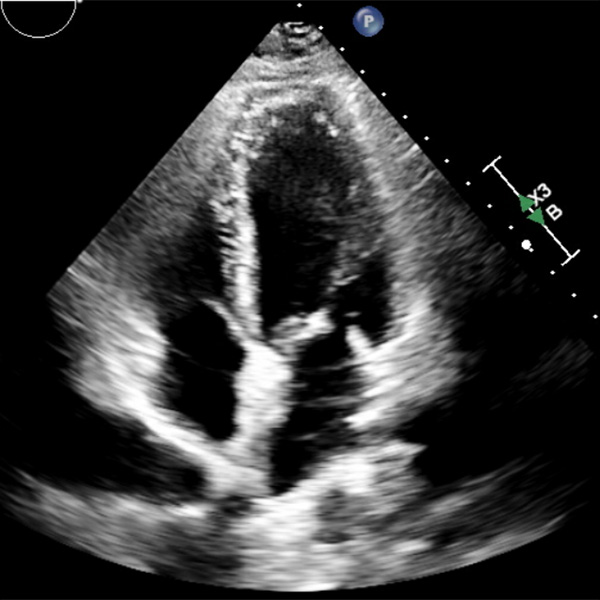

According to the American Society of Echocardiography, cardiac sonographers — also called echocardiographers — are specialists who create detailed images of a patient’s heart using non-invasive, radiation-free ultrasound equipment. The images provide detailed information about the heart’s structure, function and blood flow, which can help physicians diagnose and monitor heart conditions.

Echocardiography can diagnose conditions such as heart murmurs, valve disease and heart failure, can monitor the effectiveness of heart treatments and help assess the severity of damage following a heart attack.